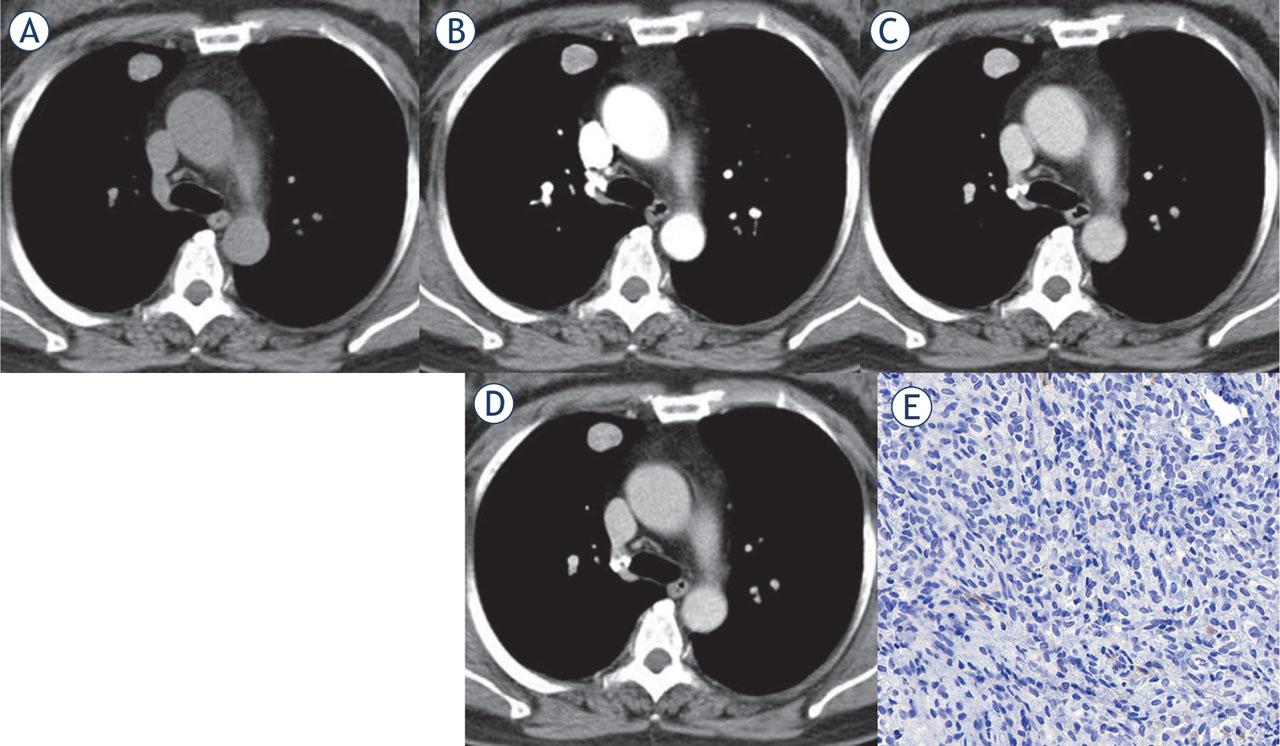

Multi-phase contrast-enhanced CT of peripheral PSP with lower Ki-67 index. Axial unenhanced CT image revealed a peripheral isodense nodule in the right upper lobe with a CT density of 46 Hu (A). After administration of the contrast medium, the lesions showed homogeneous enhancement. The lesion showed progressive and continuous enhancement in the arterial phase (73 Hu) (B) and venous phase (102 Hu) (C), with a certain enhancement washout in the delayed phase (87 Hu) (D). Immunohistochemical staining showed the Ki-67 reactive tumor cells accounted for about 1% (× 400) (E).